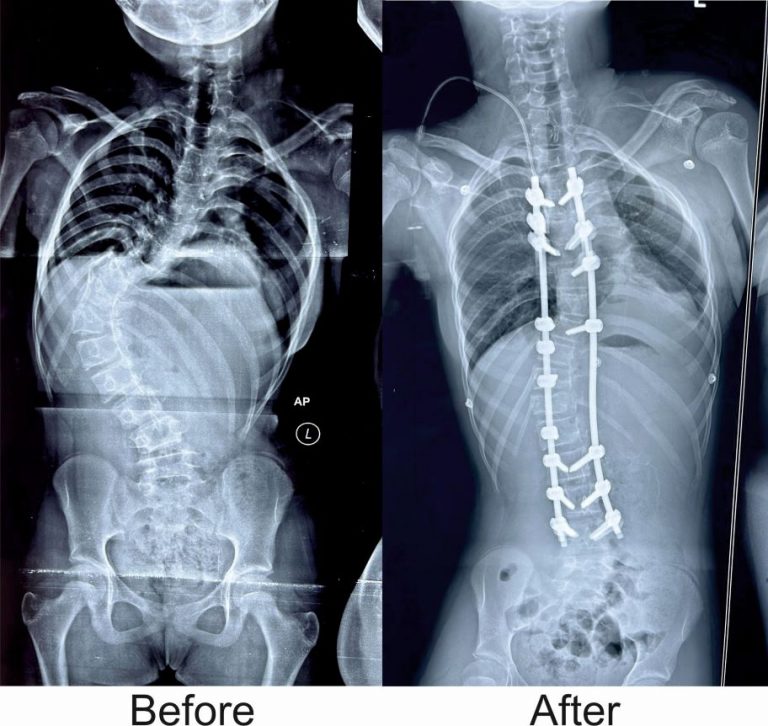

The girl was battling a spinal deformity known as Scoliosis. The abnormal curve in her spine gave it an ‘S-shaped’ appearance, threatening her promising future.

However, her spine was meticulously corrected in a recent complex operation conducted by KIMS Senior Consultant and Orthopaedic & Spine Surgeon Dr Jitendra Kumar Rout along with anaesthetist Dr Sanjeev Giri and Dr Rajmohan.

Dr Rout explained that the spinal deformity the girl suffered from is known as ‘idiopathic scoliosis’– a condition that typically develops between the ages of 10 and 15. If left untreated, it can lead to severe deformities and significantly impact self-confidence and self-esteem.